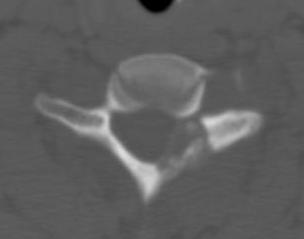

CT

Lucent lesion with nidus or calcification

Spinal lesion

- bone expansion

- intralesional stippled ossification